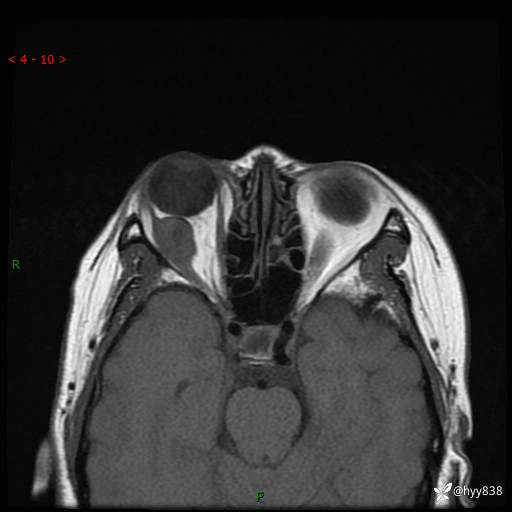

老年女性,右眼球突出1月。说说鉴别诊断,看谁第一个秒---(有结果)

主诉:发现右眼球突出1月余

简要病史:患者于1月前无明显诱因发现右眼球突出,偶感磨痛、眼胀,无视力下降,无头痛,恶心呕吐等不适。10天前就诊于当地县人民医院就诊,完善头颅ct检查,诊断为右侧眼眶肿物,建议患者上级医院进一步治疗,患者因个人原因拒绝。拟行手术,来我院就诊,门诊行相关检查后以“右眼眼眶肿物”收入院。 患病以来,患者精神饮食睡眠尚可,大小便如常、体重无明显改变。

辅助检查:MRI

临床诊断:眼眶肿物

眼眶MRI平扫+增强